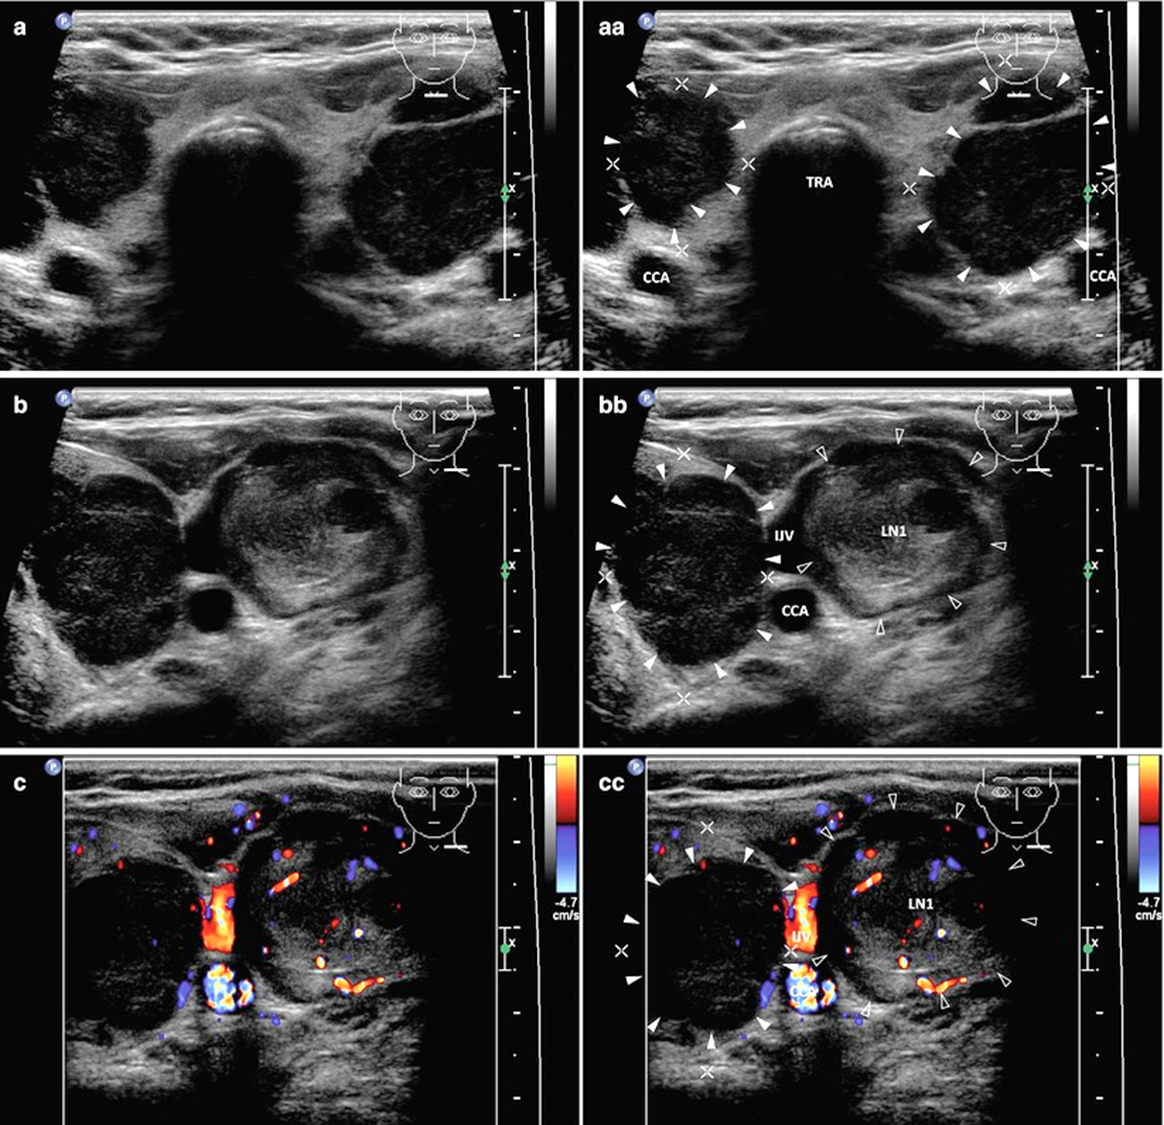

Лимфомы щитовидной железы при УЗИ

Обычно наблюдаются признаки АИТ (неоднородность структуры ЩЖ и т.д.).

Выделяют 3 варианта УЗ-картины: узловой, диффузный или смешанный.

Дистальное усиление УЗ-сигнала присутствует при всех трех типах и помогает отличить лимфому от других типов поражений щитовидной железы.

При узловом типе выявляется крупное гипоэхогенное или пониженной эхогенности образование с бугристыми контурами неоднородной структурой за счет больших анэхогенных некротических участков, а также множественных мелких гипоэхогенных включений.

При диффузном типе наблюдается двустороннее порахение с диффузной гетерогенной гипоэхогенной паренхимой, где границу между лимфомой и нелимфоматозной тканью четко определить нельзя.

Смешанный тип лимфомы характеризуется множественными неоднородными гипоэхогенными поражениями.

Могут наблюдаться признаки опухолевой инвазии и регионарная лимфаденопатия.